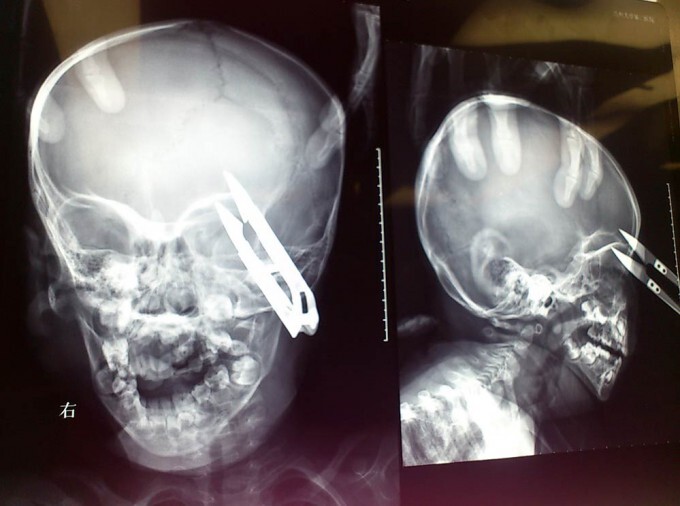

2-летний мальчик чудом выжил после того, как ножницы пронзили его голову в районе глаза. Ван Жиеронг из западной китайской провинции Ганьсу бегал по дому с ножницами, которые он нашел на столе. Неожиданно он споткнулся и упал прямо на ножницы, которые вонзились ему прямо над левым глазом

Мальчика сразу доставили в больницу университета Ланьчжоу в округе Вушань, где врачи провели срочную операцию по удалению ножниц.